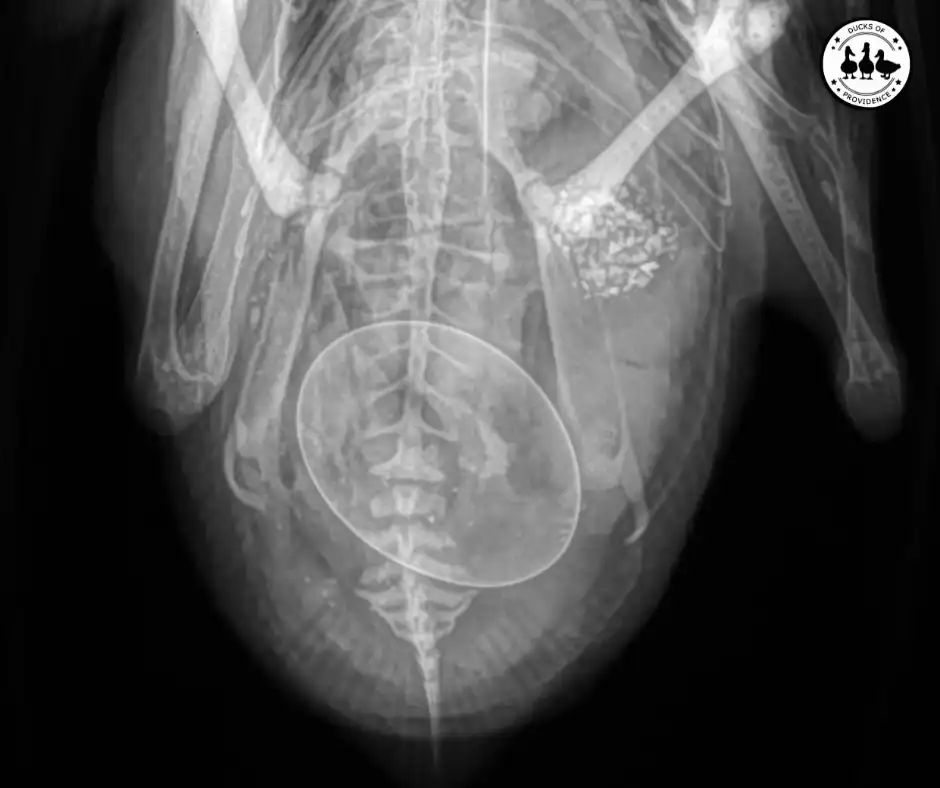

The vet carefully examined our duck and took X-rays. The latter revealed that she indeed had an egg stuck inside her. It was sideways, which is why she had so much trouble getting it out.